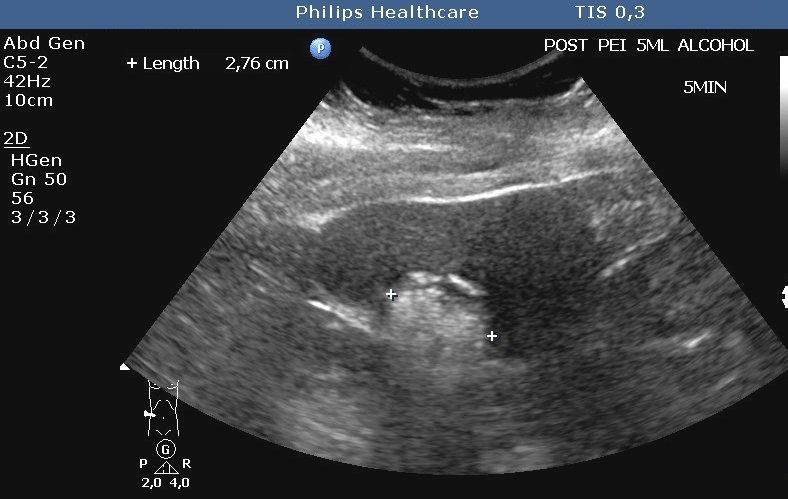

It is the most commonly used and cheapest percutaneous method for the treatment of primary hepatic cancer (HCC). Sterile, 95%, absolute alcohol is injected with US guidance to the tumor.

Ethanol causes dehydration and coagulation necrosis of the tumor cells, followed by fibrotic degeneration. After alcohol injection, a typical “snow storm like”, hyperechogenic area can be seen in the treated area (figure 15.).

Image

Figure 15. – PEIT (Percutaneous Ethanol Injection Therapy), confirmed HCC with biopsy